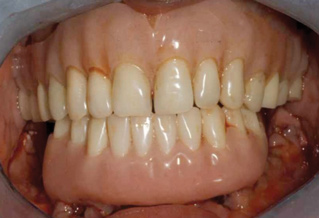

Severe maxillary atrophy may have a different etiology compared to that of the mandible, but the resultant resorption is no less debilitating. Grafting in the upper arch is increasingly less common with the advent of implant types such as zygoma that are anchored in remote bone and offer a far less traumatic and functionally improved option, especially for an aging patient. This is illustrated in Figure 4 and Figure 5. The patient had worn both a removable partial denture and full lower denture for more than 40 years with resulting severe maxillary atrophy opposing a natural dentition. Four zygoma implants were placed using the "quad" approach9,10 in lieu of a bone graft procedure (Figure 4). The final restoration remains in function in the patient's seventh decade (Figure 5).

Fig 5. Final restoration remains in function.

Figure 5